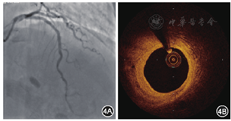

2018年4月13日行冠状动脉造影检查,结果显示:左主干正常;左前降支近段支架内无再狭窄,中远段狭窄程度为40%;左回旋支远段狭窄程度为70%;右冠状动脉近远段狭窄程度为20%~30%;血流TIMI分级均为3级。OCT检查结果示左前降支原支架无再狭窄,内膜覆盖完全,96.3%降解吸收,平均管腔面积为6.50 mm2,最小管腔面积为5.11 mm2,斑块负荷为34.8%,新生内膜面积为2.78 mm2(图4)。术后口服阿司匹林肠溶片100 mg(每天1次),瑞舒伐他汀钙片10 mg(每晚1次)。

本例患者置入生物可吸收支架前,对靶血管进行了充分的预扩张,保证释放支架成功。释放支架后用后扩张球囊进行整形,以保证支架完全贴壁。OCT检查示平均管腔面积为7.15 mm2,最小管腔面积为5.85 mm2,斑块负荷为18.6%。术后1年复查OCT,平均管腔面积为5.78 mm2,最小管腔面积为4.86 mm2,斑块负荷为30.6%,新生内膜面积为2.84 mm2。术后3年复查OCT,平均管腔面积为6.50 mm2,最小管腔面积为5.11 mm2,斑块负荷为34.8%,新生内膜面积为2.78 mm2。结果显示,可吸收支架术后3年吸收率为96.3%,管腔增大。